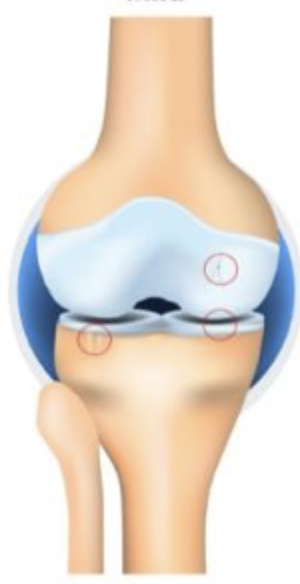

grade 1

Which stage of OA is characterized by possible osteophytic lipping and doubtful JSN

grade 2

Which stage of OA is characterized by definite osteophytes and possible JSN